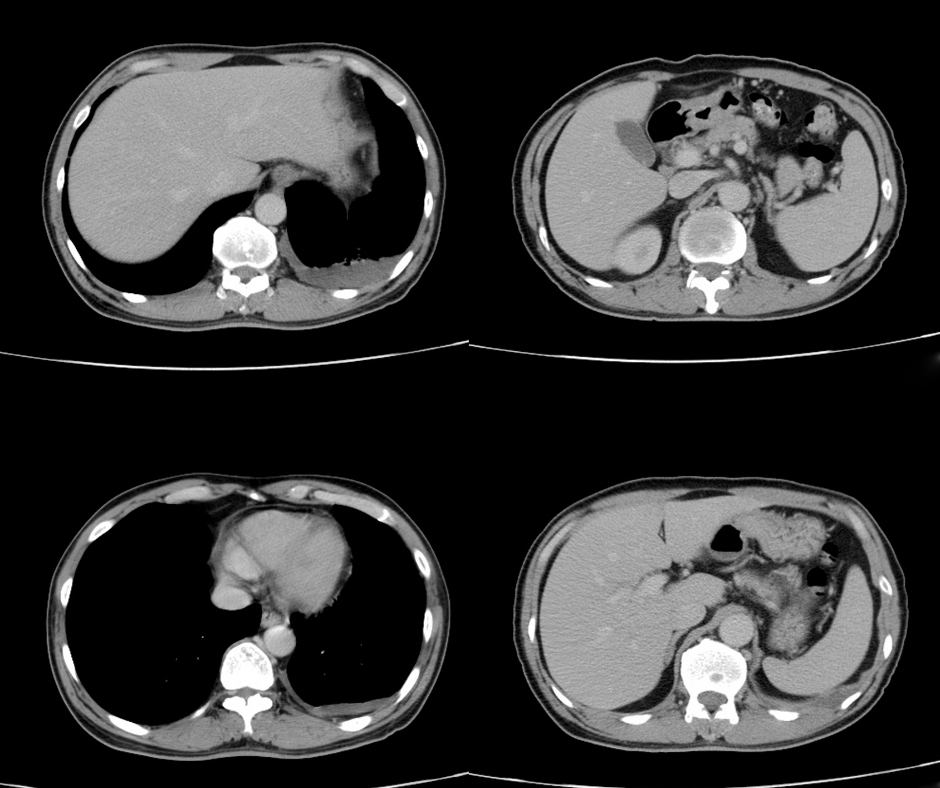

Modifications to pack-year history and smoking quit duration thresholds beyond those recommended in the 2021 United States Preventative Services Task Force (USPSTF) criteria for low-dose computed tomography lung cancer screening may more than double the number of increased lung cancer cases physicians would see with application of the 2021 USPSTF screening criteria.